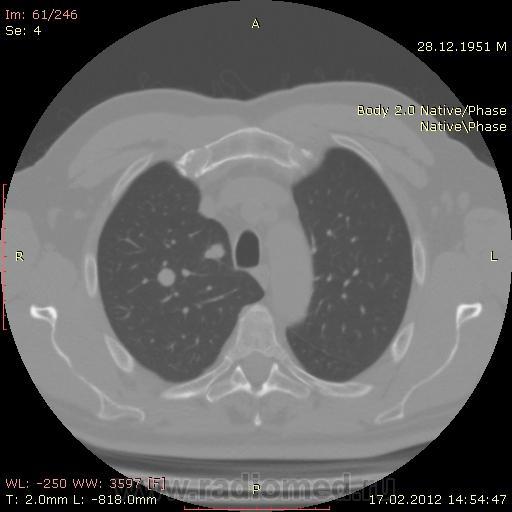

КТ.

В феврале 2012 года при очередном флюрографическом обследовании были обнаружены изменения в лёгких. По собственной инициативе было сделано КТ лёгких.

На первый взгляд - метастазы. А так, если родственник, искать выходы на МСКТ.

Согласен с Андреем Юрьевичем - наиболее вероятно - это метастазы...исключите первичное новообразование почки.

Согласен с коллегами, внешне вылитые метастазы. Но почему нет контраста? Не соли мочевой кислоты точно. Учитывая анамнез можно думать о неопроцессе почек.

Повторяюсь (мнение озвучил еще до КТ и до Ваших коментов) но это отдаленные по времени метастазы рака почки....увы....и даже если будет найден еще один первичный очаг, то все равно это - метастазы...опять - увы....